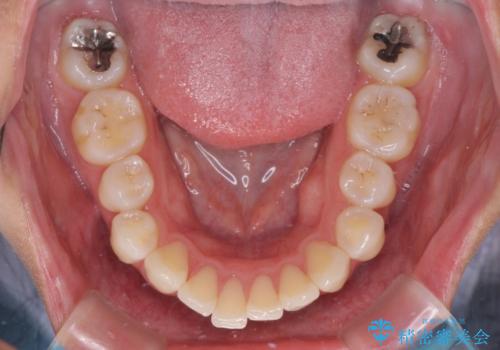

- 抜歯矯正の後戻りで前歯が突出してきていることを気にして来院された患者様です。

口元の突出感を改善するにあたり、抜歯矯正は行うことができないため、奥歯の後方移動とIPR(歯と歯の間を削る)により達成することとしました。

再度後戻りしたときに対応しやすいよう、インビザラインにて矯正治療を行うこととしました。

しっかりと装着時間を守り、ゴムかけにも協力していただいたので、口元を引っ込めることができました。